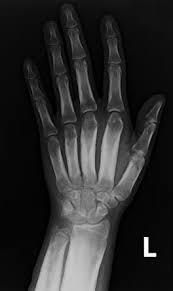

Ulnar variance–what happens with postive and negative?

Positive ulnar variance can cause ulnar impaction syndrome: proximal lunate develops sclerosis, subchondral cysts, and osteophytes

negative ulnar variance: get ulnar impingement syndrome: see edema and degenerative change in ulna/radius.

Can also see lunate osteonecrosis (keinboch malacia..sclerosis + edema in lunate)